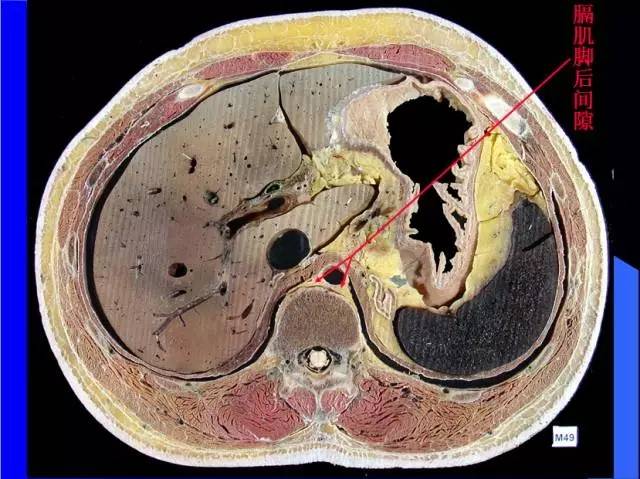

肺部基础X片及CT片解读